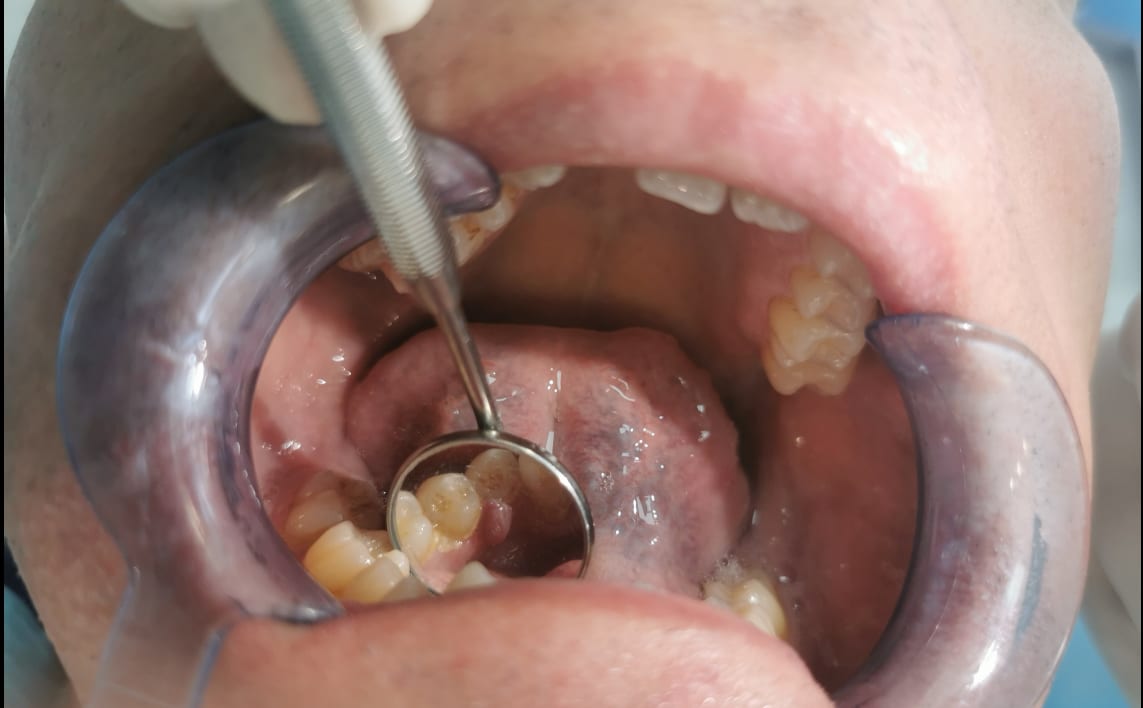

le premier, patient de 58 ans qui a une boule au niveau de la gencive en lingual de 44

Elle est apparut avant fevrier , pas douloureuse,saignement lors du brossage , gonfle et degonfle selon le patient,

pas de sondage, molle, mobile, un peu comme pediculée.

les dents adjacentes sont vitales, détartrage fait dans la séance ;